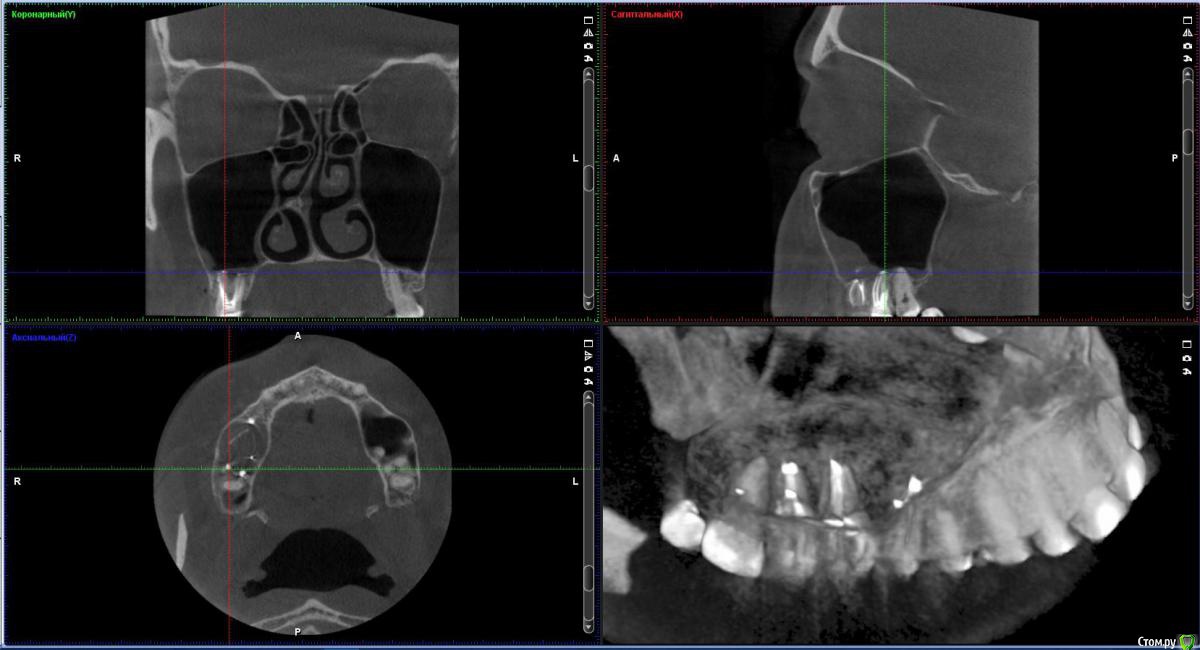

vicTORYa Опубликовано 23 октября, 2016 Автор Поделиться Опубликовано 23 октября, 2016 Скажите пожалуйста понятно ли что-то на этом КТ?С момента их лечения прошло чуть больше года, ждала не ставила коронки посмотреть не дадут ли проблемы зубы, в которых выведен материал, можно ли на данный момент сделать какие-то выводы? 6 и 7 не беспокоят, а вот 5 немного побаливает иногда. Просто иду на следующей неделе ставить коронки, всё ли в порядке с зубами, можно ли ставить коронки? Перелечивать так на всякий случаи не хочется, а только если там возникнет проблема. У мужа тоже есть один зуб с выведенным материалом и ему уже больше 10 лет и нет с ним проблем. Вот и думаю перелечивать только в случае необходимости.Сделать новый ренген не могу очень много уже сделал ренгенов за этот год. Ссылка на комментарий

IvanK Опубликовано 24 октября, 2016 Поделиться Опубликовано 24 октября, 2016 если зубы болят, то одевать на них коронки нельзяВарианта два: повторное лечение или удаление Ссылка на комментарий